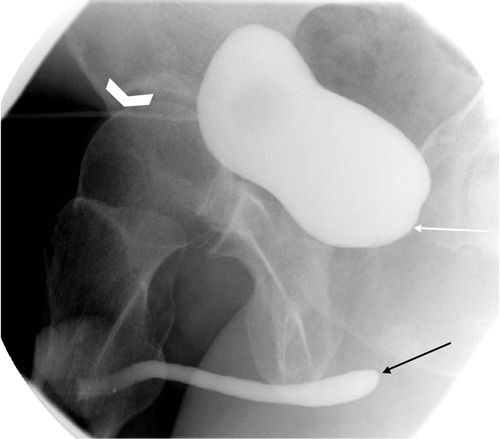

Figure 6: Oblique view of an ascending urethrogram demonstrating an abrupt

cut off of contrast at the proximal end of the urethra (arrow).

Figure 7: Oblique view following suprapubic catheter insertion (chevron) demonstrating contrast within the urinary bladder, but no connection between the base of the bladder(white arrow) and the urethra (black arrow), due to urethral transection.